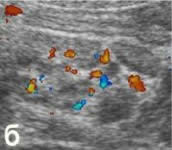

б - ДДС в энергетическом режиме. Определяется гиперемия

червеобразного отростка (поперечный срез). |